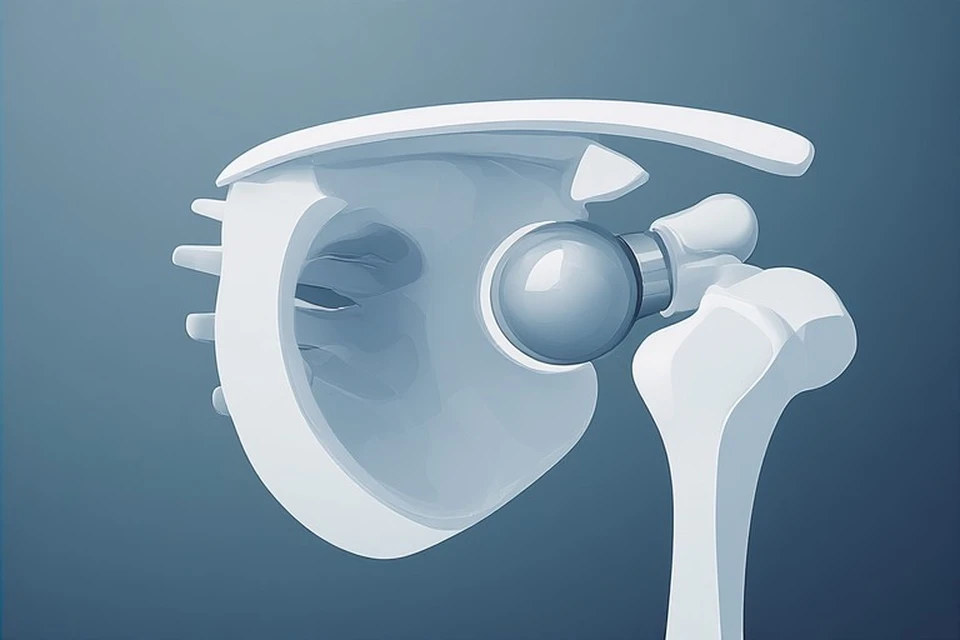

Эндопротезирование плечевого сустава

Во время операции разрушенные части плечевого сустава заменяют искусственными компонентами. Обычно речь идет о головке плечевой кости и суставной поверхности лопатки, но точный объем зависит от того, какая зона пострадала сильнее и насколько сохранены окружающие сухожилия. Цель вмешательства в том, чтобы уменьшить боль и вернуть суставу рабочее движение.

Такую операцию чаще рассматривают при выраженном артрозе, тяжелых последствиях переломов, асептическом некрозе (гибели участка кости из-за нарушения кровоснабжения), а также при повреждении вращательной манжеты плеча (сухожилий, которые помогают поднимать и удерживать руку). Не у всех пациентов подходит один и тот же вариант замены. Иногда выполняют частичное протезирование, иногда полное, а при выраженном повреждении сухожилий используют обратный протез.